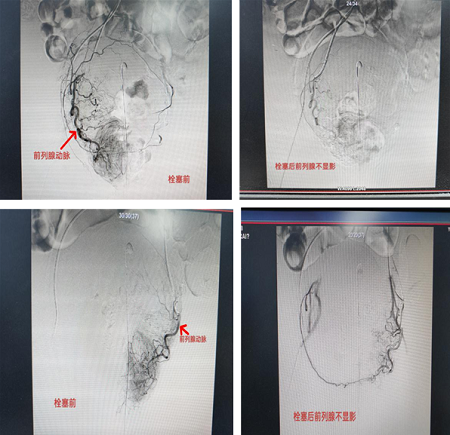

患者男性、60岁,因急性心肌梗死,收住心内科CCU抢救,经溶栓抢救治疗,挽救了患者的生命,正在大家庆幸的时刻,患者突然出现大量血尿,血红蛋白由131g/L降到65g/L,出血量估计大约2000ml以上,再次危急患者生命情况出现了,患者病情紧急、危重,医院组织多学科会诊,考虑前列腺大出血,该患者因心肌梗死,出血不能内科止血,因溶栓更容易出血,不能行外科手术,经过我科杨亚平主任医师会诊后,拟行“超选择性前列腺动脉栓塞术(prostaticarteryembolization PAE)”,解决了“两难问题”,手术顺利完成,患者安返病房。

前列腺动脉栓塞术(prostaticarteryembolization PAE)可以使前列腺缺血性萎缩,有效治疗了前列腺增生,解决了男性老年人的“老大难问题”,从而提高生活质量,前列腺动脉栓塞术是前列腺增生较为理想的一种治疗方法,该患者的生命得以救治,介入手术治疗起到了关键作用。目前该患者生命体征平稳,正在康复中。

近年来,随着介入放射学快速发展,介入治疗技术已应用到急救医学领域,并发挥着极其重要的作用,此项技术具备诊断和治疗两种功能,使得动脉性出血的急诊(症)患者能够得到快速的诊断和治疗,该患者能快速恢复,介入“前列腺造影+栓塞术”起到了关键性作用。